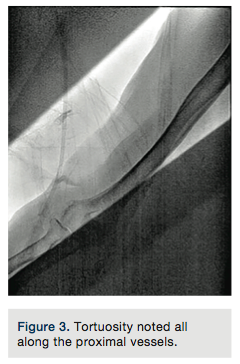

The right radial artery was punctured using counter-puncture technique and a .021-inch micropuncture guide wire was placed in the Teflon cannula. Mild difficulty was encountered at the first attempt to advance the wire. The guide wire was withdrawn and a low-pressure manual injection radial angiogram was performed. A perforation was noted at the distal radial artery (Figure 1). In an attempt to obtain control of the radial artery lumen, a .014-inch guide wire was placed in the access cannula and attempts were made to navigate the lumen, with further resistance. A new area of perforation was noted proximal to the previous site of extravasation (Figure 2). After several attempts, the .014-inch guide wire was placed in the subclavian artery successfully. Tortuosity was noted all along the proximal vessels (Figure 3).

The most common etiology of radial artery perforation is guide wire-related trauma. A J-tipped guide wire ‘engaging” a small side branch is frequently presumed to be a cause for “cryptogenic” perforations. In this instance, difficulty in advancing the guide wire with likely side branch trauma or subintimal placement would have resulted in perforation. As recommended, the operators performed a radial angiogram when they encountered resistance to advancement of the guide wire (Figure 1). Appropriately so, instead of abandoning the access site, they elected to gain control of the arterial lumen and succeeded (Figure 3).1,2 Perforation being the immediate issue at hand, a catheter was placed through the perforated segments and the procedure was